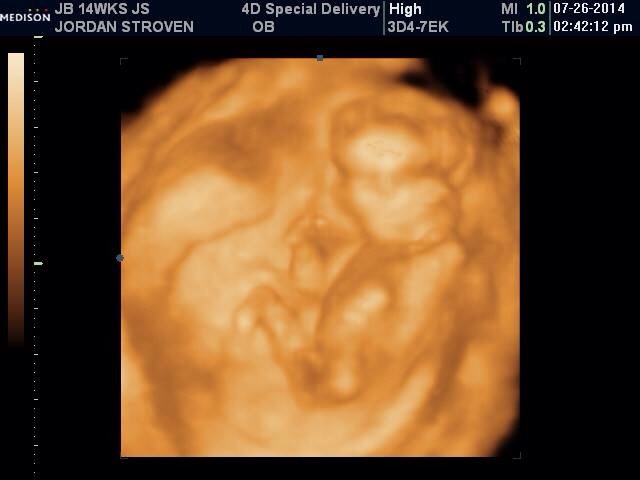

Hi ladies! I just found this site today and I'm so excited and wish I would have found it sooner!! I have a few pictures I'm going to try and upload, one is from my Dr at 12w5d just to show the skull and nub theory, I'm not great about that but just maybe to help. Lol the next is at 13w5d from an elective scan I had to try and see the gender. They leaned towards girl but I'll confirm with my actual Dr sep 5th, it's killing me waiting though! I've had mixed reviews from everyone I've shown! Some say girl, some say boy, some say to keep receipts of I buy pink.... It's so confusing! I wouldn't be so doubtful I think had so many people question the scan, and the fact it took forever to even get a hint! Baby was stubborn! It was supposed to take 15 minutes, took 45.... Two techs.... Me having to get up and move around multiple times. Lol it was a show!

I'm thinking this probably should have been done on my laptop now. I can't organize them very well on my phone, the side view on 2d was at 12w5d everything else like the 3d and between the leg shots were all taken 13w5d I hope that makes sense!